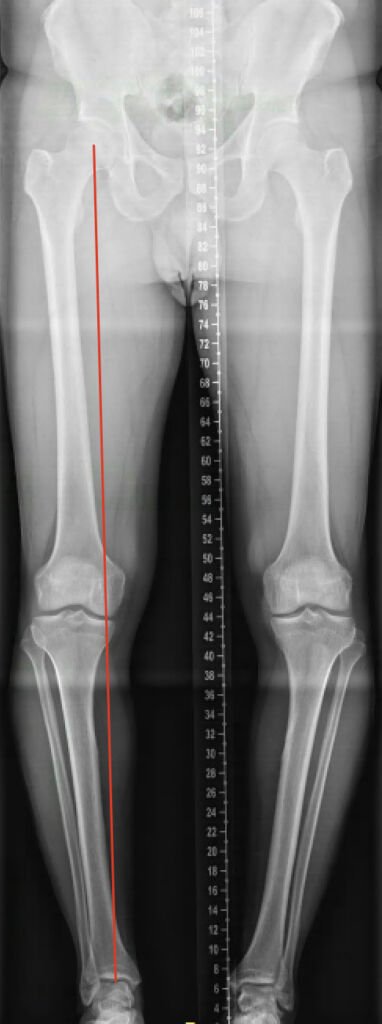

Varus

Dit is een typisch voorbeeld van een varus beenas, waarbij de belasting meer aan de binnenkant zit (rode lijn). Na de ingreep is de belastinglijn verplaatst.